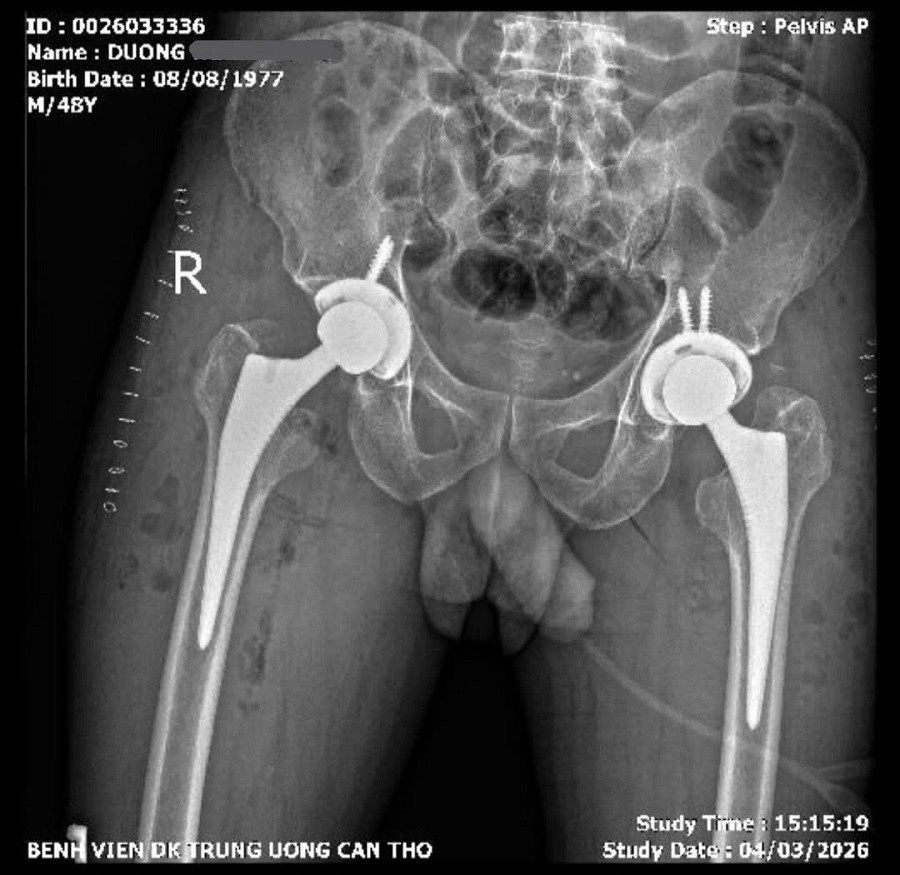

X-Quang khung chậu kiểm tra sau phẩu thuật

Các bác sĩ đã lựa chọn đường mổ trực tiếp phía trước – phương pháp phẫu thuật ít xâm lấn trong thay khớp háng. Ca mổ kéo dài khoảng 04 giờ, tiến hành thay khớp háng hai bên trong cùng một lần phẫu thuật.

Sau phẫu thuật, bệnh nhân phục hồi thuận lợi và đến ngày thứ 02 đã có thể tập đi lại với khung hỗ trợ và tự đi không cần dụng cụ hỗ trợ sau 05 ngày,dự kiến ra viện ngày 11/3/2026